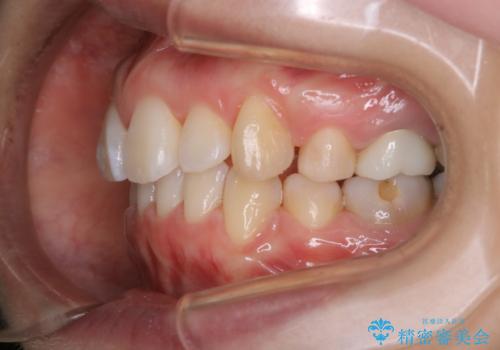

- 全体的に着色が付いているのが気になるとのことで来院されました。

PMTC60分コースを行いました。

着色がかなり頑固なため、エアフローも使い着色を除去していきました。

下の前歯にはかなり多くの歯石が付いており、デンタルフロスでもう少し防げるため、使用法や頻度を確認しました。

インビザラインの矯正治療は、マウスピースの使用時間が少ないとマウスピースと歯のフィッティングが悪くなりシュミレーション通りに歯が動かなくなるため、追加アライナーといって、再度スキャニングを行い新しいフィットの良いマウスピースに変えていきます。そのスキャニング時にアタッチメント(歯の表面に付いた突起)も除去するため、そのタイミングでクリーニングするのもおすすめです。